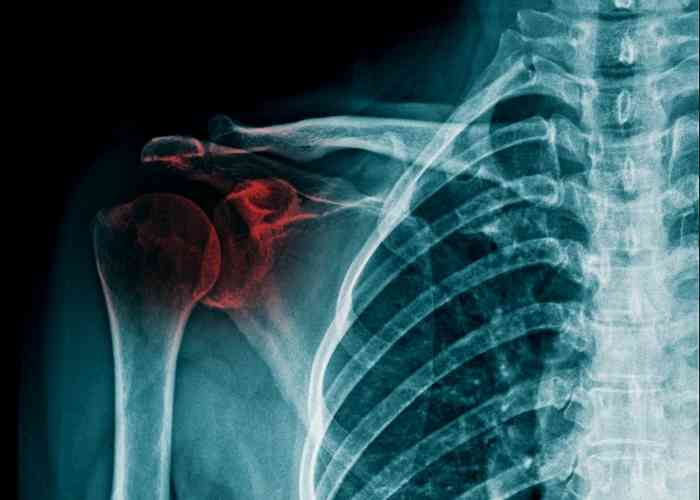

사고로 어깨뼈가 골절되었을 때, 관련된 입원 기간, 수술 후 물리치료 및 도수치료 비용, 그리고 실비보험 적용 여부에 대해 알아보겠습니다. 어깨 골절은 예상치 못한 상황에서 찾아올 수 있으며, 대비하기 어려운 사건입니다. 저 또한 몇 년 전에 어깨뼈 골절로 인한 치료를 받은 적이 있습니다. 이 글에서는 어깨뼈 골절 치료와 관련된 주요 내용을 다룰 것입니다.

어깨뼈 골절의 입원 기간은 다양하며 상황에 따라 다를 수 있습니다. 일반적으로 어깨 골절의 경우 상완골 골절로 분류되며, 핀고정 수술이 필요한 경우 보통 1주에서 2주 정도의 입원 기간이 필요합니다. 그러나 교통사고나 다른 상황으로 어깨뼈 골절이 더 복잡한 경우에는 입원 기간이 더 길어질 수 있습니다. 따라서 개별 환자의 상태와 치료 방법에 따라 입원 기간이 결정됩니다.